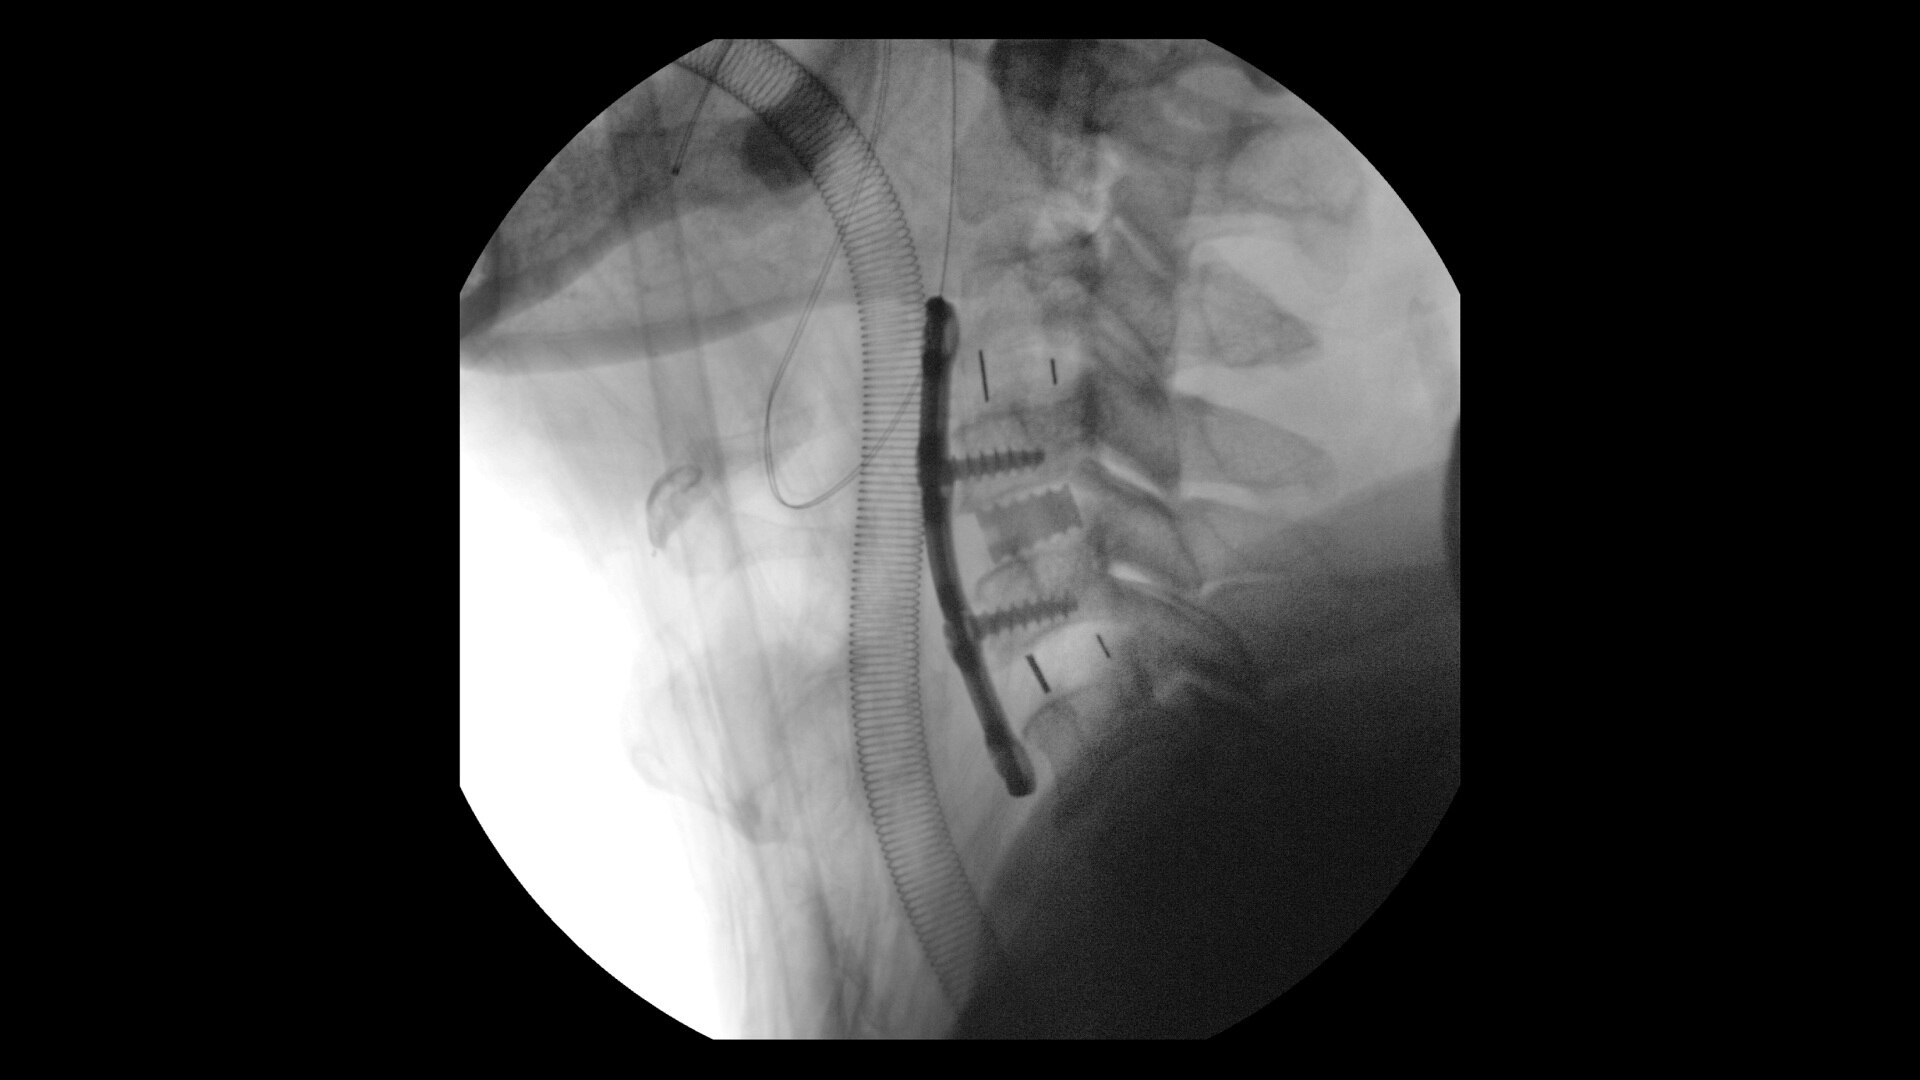

Expansive volumes

See more levels during a spinal fusion, or more of the pelvis or femur during an orthopedic procedure. With a 19 cm x 19 cm x 19 cm volume, OEC 3D captures a 67% greater volume than other 3D C-arms*.

Precise analysis

Enhance intraoperative decision-making with visualization capabilities of Augmented Fluoroscopy in the OEC 3D Volume Viewer. Analyze five perspectives with 3D imaging tools including Multi-Oblique Mode, scrolling 512 slices, zoom, and more.